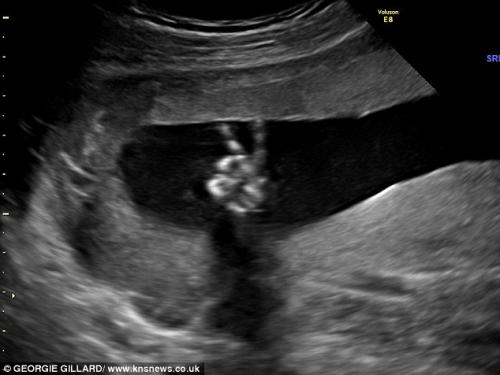

Бебе ги смирува родителите со знакот за мир и победа!

Ed и Dee Parsons како и многу други родители биле нерозни кога требало да отидат на преглед со ултразвук во 20-та недела од бременоста. Но, нивните грижи брзо исчезнале кога виделе како нивното бебе со рачето го прави знакот "V", кој симболизира победа и мир.

Знакот бил направен толку јасно со малите прстиња за време на ултразвукот, што родителите го прифатиле како знак дека нивниот син им порачува дека е добро и да не се грижат.

Лекарката, која го правела ултразвукот не можела да поверува и вели дека никогаш претходно не видела нешто такво.